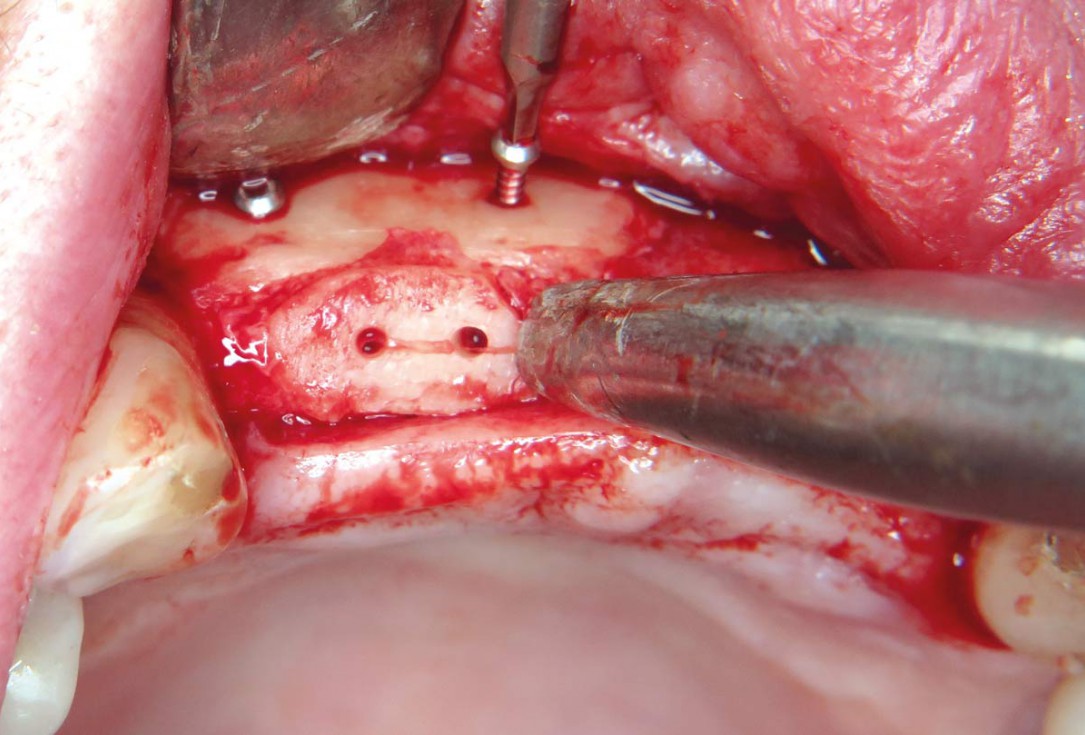

14 / 22 - Removal of the osteosynthesis screws

Three-dimensional augmentation with maxgraft® cortico - M.Sc. E. Kapogianni

15 / 22 - Excellent osseous integration of allogenic cortical plates